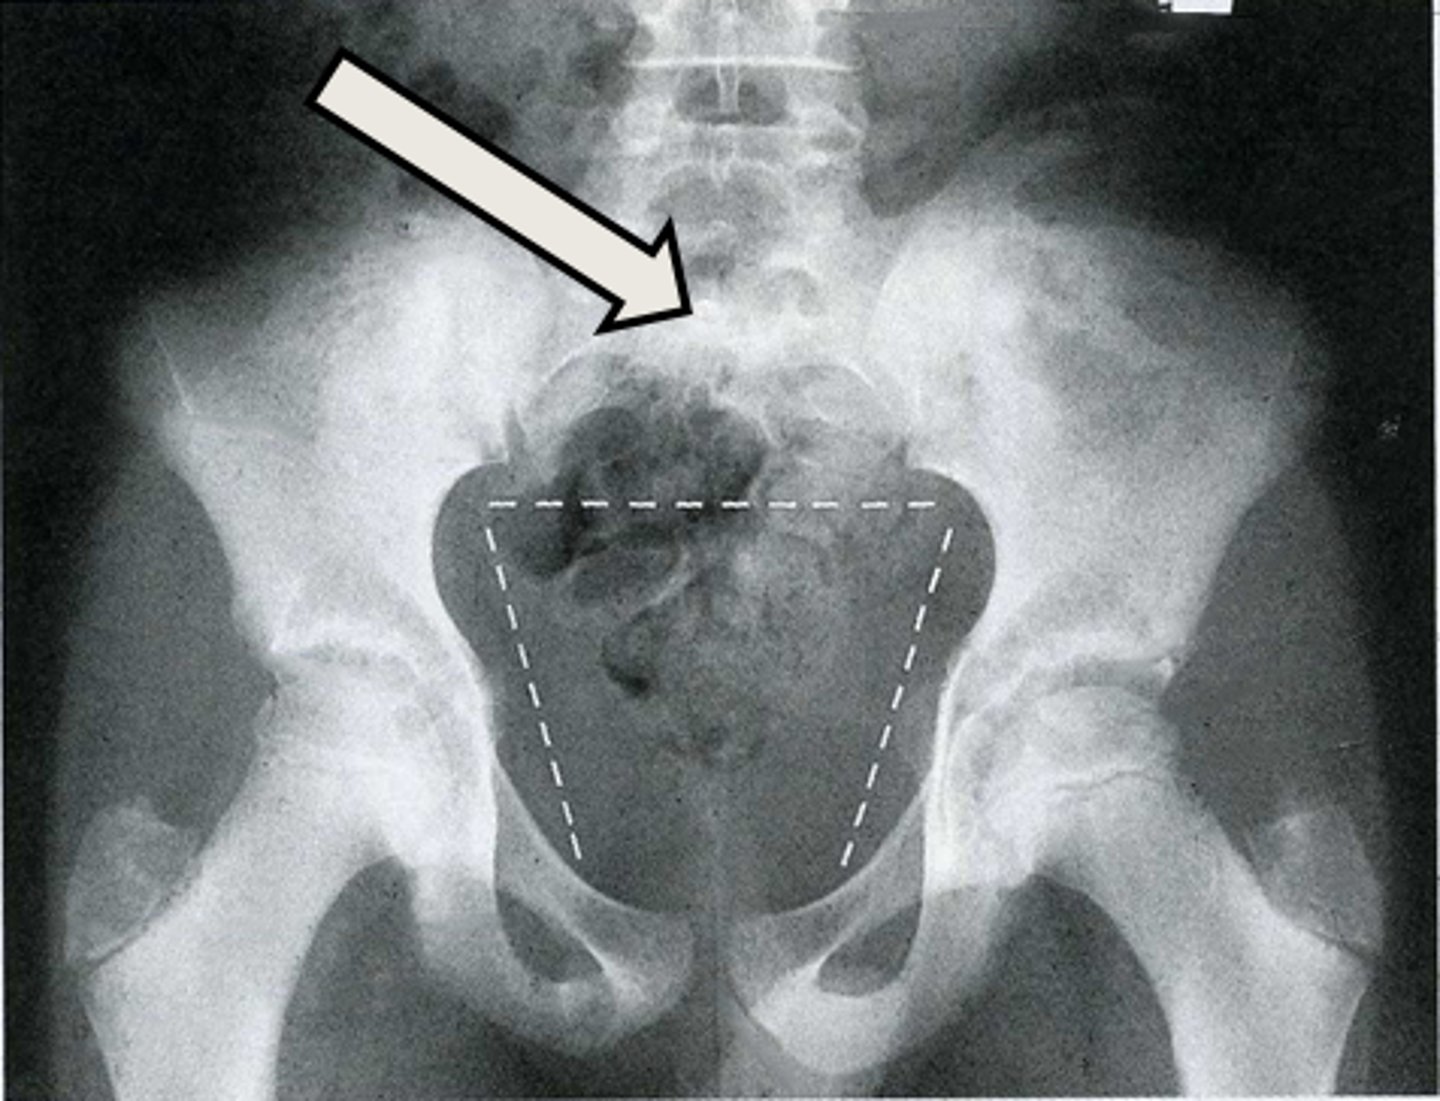

AP pelvis

What is the image?

R sacroiliac joint

What is indicated in the image?

Sacrum